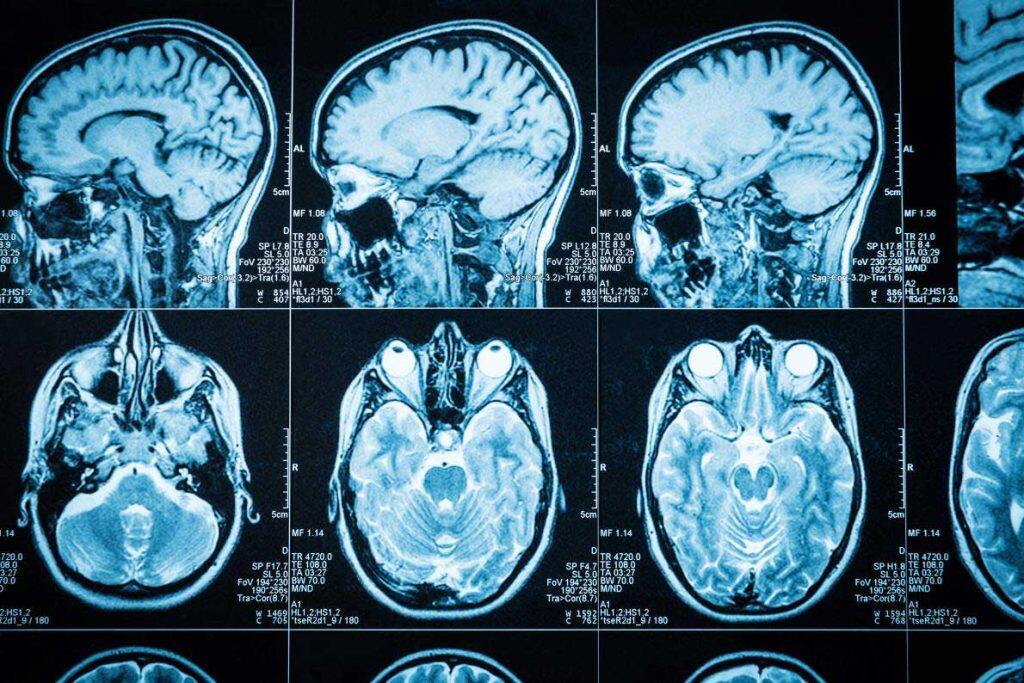

The University of Edinburgh is part of a new collaborative research agreement that aims to transform care for people living with dementia.

The collaboration, named NEURii, will explore the use of data and digital solutions to complement approved treatment options for patients and solve issues related to the prediction, prevention, management, and treatment of dementia.

It aims to translate world-class data, neurology and digital sciences into projects that can enhance the quality of life of people living with dementia.

NEURii will use high-quality data, artificial intelligence and machine learning to deliver initial pilot projects that have the potential to make a meaningful difference to patients’ lives while maintaining data security and public trust.

By combining diverse digital biomarkers that can be acquired non-invasively in real world clinical and non-clinical settings (e.g. speech from conversation) with health data, and analysing them with tailored AI algorithms, NEURii will create innovative digital solutions.

It is estimated that more than 55 million people are currently living with dementia in the world and nearly one million in the UK, and this number is expected to grow rapidly.

Providing data-driven solutions that complement existing treatments could help to improve earlier detection and diagnosis, evidence-based treatment decision-making, monitoring of disease progression and maintenance of quality of life.